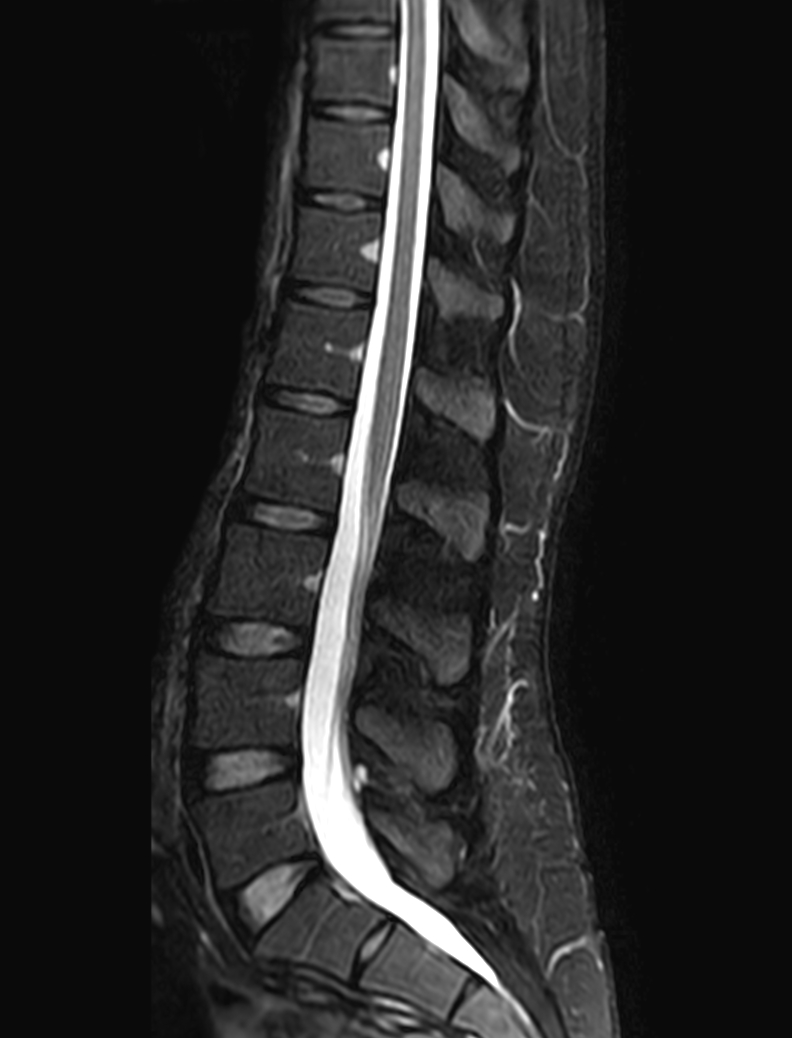

Sagittal STIR TSE